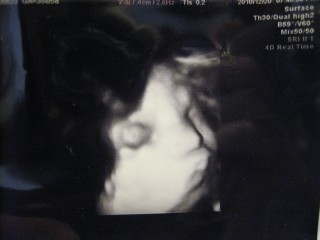

今日は顔がすごくきれいに写りました!! 推定体重は2587g大きくなったなぁ~(´∀`) 早く会いたいね~(* ̄∇ ̄*)